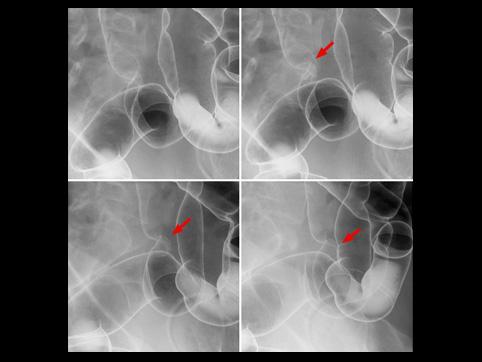

疾病(病理主体)的分类恶性上皮性肿瘤/腺癌

部位(按器官分)大肠/乙状结肠

检查方法X线

肿瘤的肉眼分类1型(肿瘤型)/

肿瘤最大直径10~14

肿瘤的深度ss(a1)